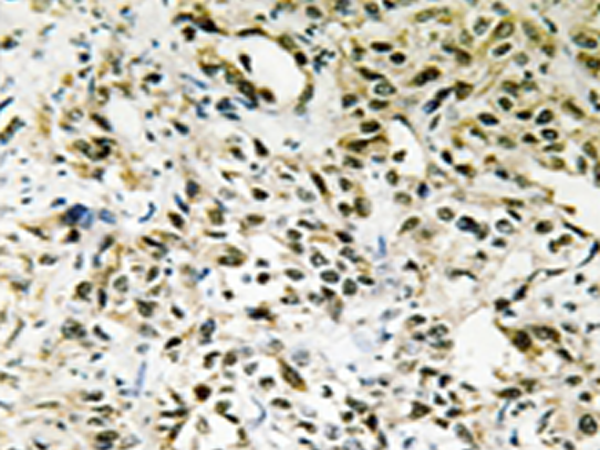

IHC positive control: |

Human liver carcinoma tissue |

IHC Recommend dilution: |

50-100 |